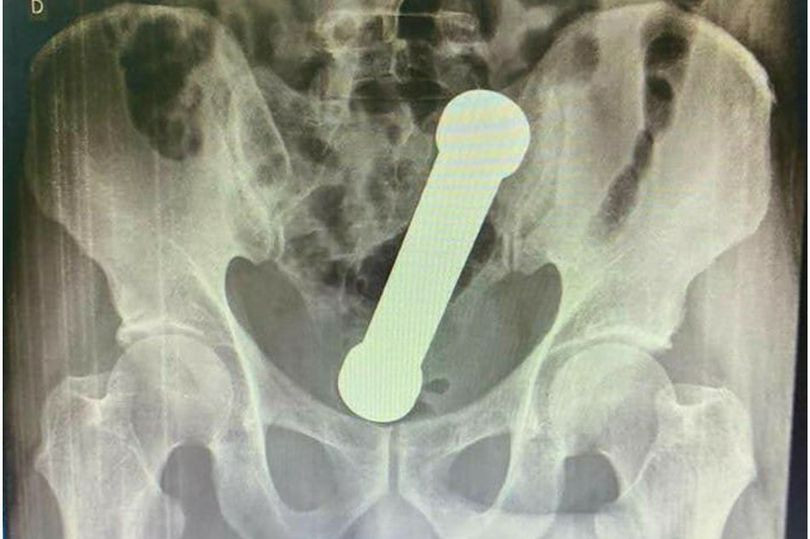

However, he couldn’t stay calm enough for the medics to examine him so they opted to X-ray his abdomen and what they saw was shocking!

They saw a large object hanging in the 54-year-old man’s rectum, which was later discovered to be a dumbbell after it was extracted.